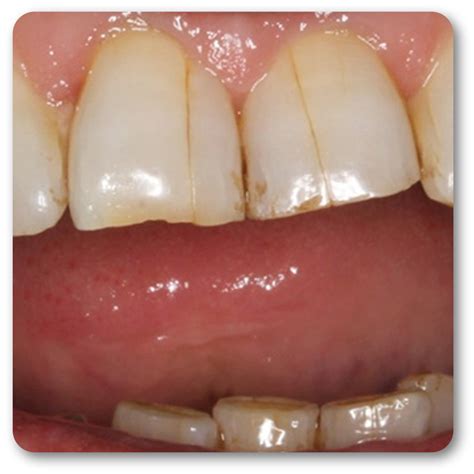

Craze Lines Tiny cracks only in the outer enamel. Generally harmless. Usually no treatment needed; cosmetic only.

A crack in tooth does not always cause pain, which makes it tricky to identify. Sometimes the crack is so small (a craze line) that it is only visible to a dentist. Other times, the symptoms are unmistakable. Watch for the following warning signs: